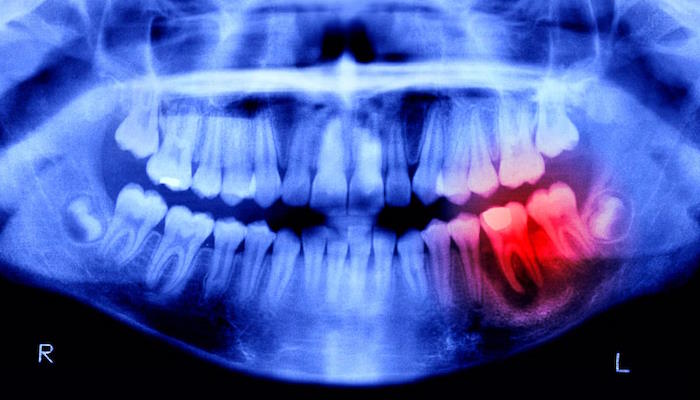

Зубы, однако, не являются костями. Хотя они сделаны примерно из того же материала и являются самым твердым материалом в организме человека (благодаря защитному слою эмали), они лишены важнейшей способности к самовосстановлению. Но это не всегда так. Японские исследователи разрабатывают экспериментальный препарат, который обещает восстановить человеческие зубы. Испытания на людях начались в сентябре 2024 года.

Это открытие стало результатом многолетних исследований, посвященных особому антителу под названием "Ген–1, ассоциированный с маточной сенсибилизацией" (USAG-1), которое, как было показано, ингибирует рост зубов у хорьков и мышей. Еще в 2021 году ученые из Киотского университета, которые также будут участвовать в будущих испытаниях на людях, обнаружили моноклональное антитело (метод, обычно используемый для борьбы с раком), которое нарушило взаимодействие между USAG—1 и молекулами, известными как костный морфогенетический белок, или BMP.

Теперь ученые увидят, насколько они похожи, потому что люди проходят аналогичное испытание. Это исследование длилось 11 месяцев и было посвящено 30 мужчинам в возрасте от 30 до 64 лет, у каждого из которых отсутствовал как минимум один зуб. Препарат будет вводиться внутривенно, чтобы доказать его эффективность и безопасность, и, к счастью, в предыдущих исследованиях на животных не сообщалось о каких-либо побочных эффектах.

Если все пойдет хорошо, больница Китано будет проводить лечение пациентов в возрасте от 2 до 7 лет, у которых отсутствуют как минимум четыре зуба, с конечной целью получить лекарство для восстановления зубов к 2030 году. Хотя в настоящее время эти методы лечения предназначены для пациентов с врожденной зубной недостаточностью, Такахаши надеется, что они будут доступны всем, кто потерял зуб.